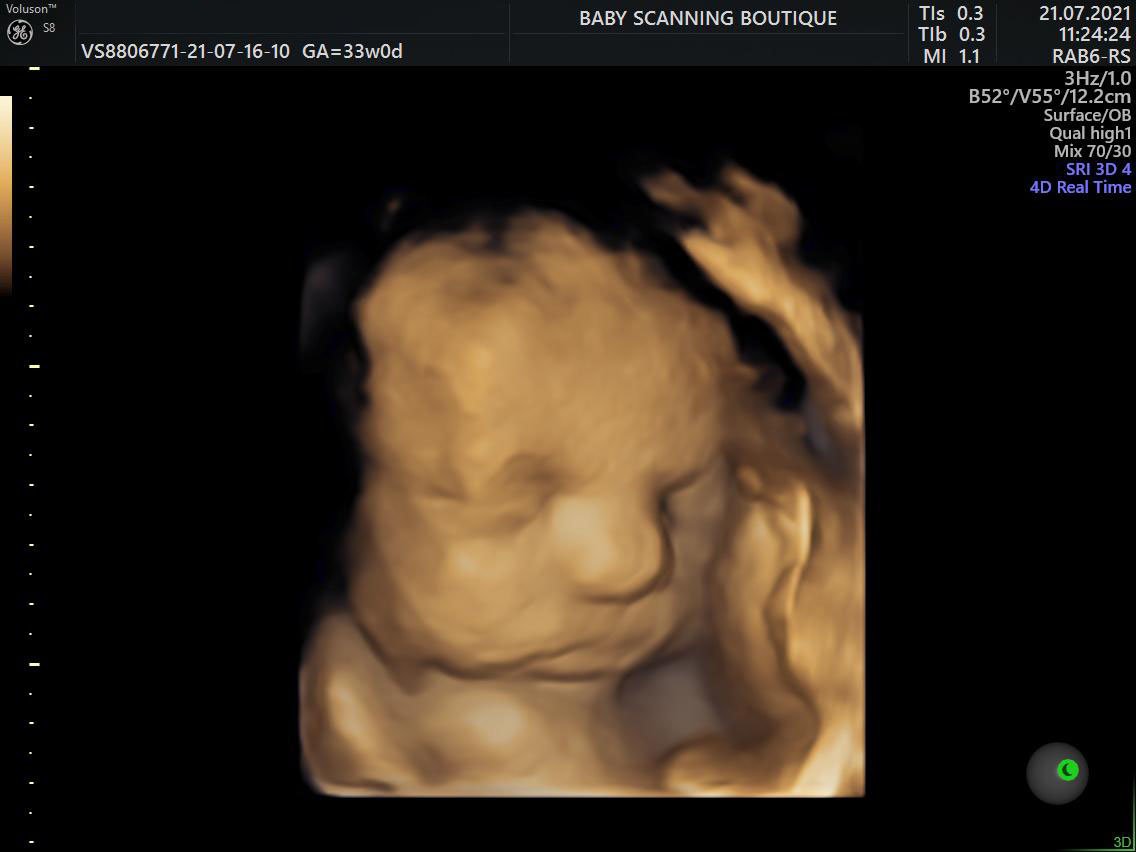

These are usually the 2D black and white scan images you are probably used to seeing in the hospital. This is because at this early stage baby isn’t yet developed enough to see in more detail. The same technology (ultrasound machine and probe) is used later in your pregnancy but is capable of showing you much more detail once your baby is sufficiently developed, usually this is possible from around 16 weeks but best images are taken around 27 weeks. These are the high detail 3D pictures that have a golden look and feel to them.

HD Live is an enhanced version of a 3D scan using the latest GE technology available on only the newest machines to render amazingly realistic images of your baby. It uses the most recent generation of beamforming technology combined with speckle reduction algorithms and virtual light sources to create lighting and shadowing effects. This means our sonographer can incorporate light and shadow on baby’s face just as you would see in a person standing next to you.

Our 3D and 4D bonding scans allows you see your baby at an enhanced level of detail, meaning you can see things that cannot be seen in traditional 2D format such as sucking their thumb, smiling, blowing bubbles or opening their eyes.

The perfect time for a 4D bonding scan is between 26-31 weeks because of the optimal balance between baby development and womb conditions but 4D scans can be done anytime from 14 weeks and even as late as 36 weeks we can still get amazing quality images.

The GE Voluson ultrasound machine we use is a very sophisticated piece of technology, its widely recognised worldwide as for providing the best 4D images and you’ll be amazed by the depth of clarity and detail it shows off. In 4D its possible to see your baby do things like sucking their thumb, opening their eyes, blowing bubbles, smiling etc… perfect to start getting to know your baby before he/she is even here.